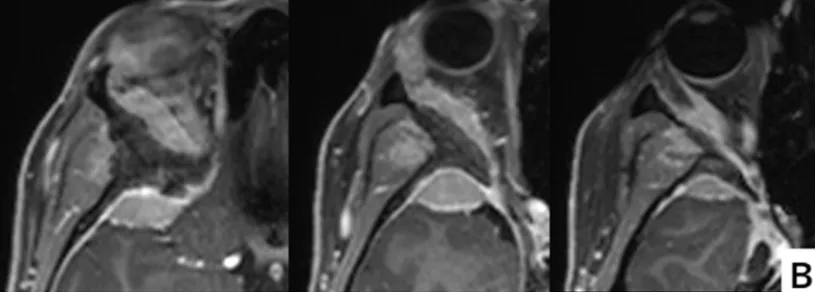

术前增强MRI显示蝶眶脑膜瘤从眶上壁延伸至外侧眶壁以及眶周。颞极硬膜和颞肌也被浸润。眼眶受压导致眼球突出。